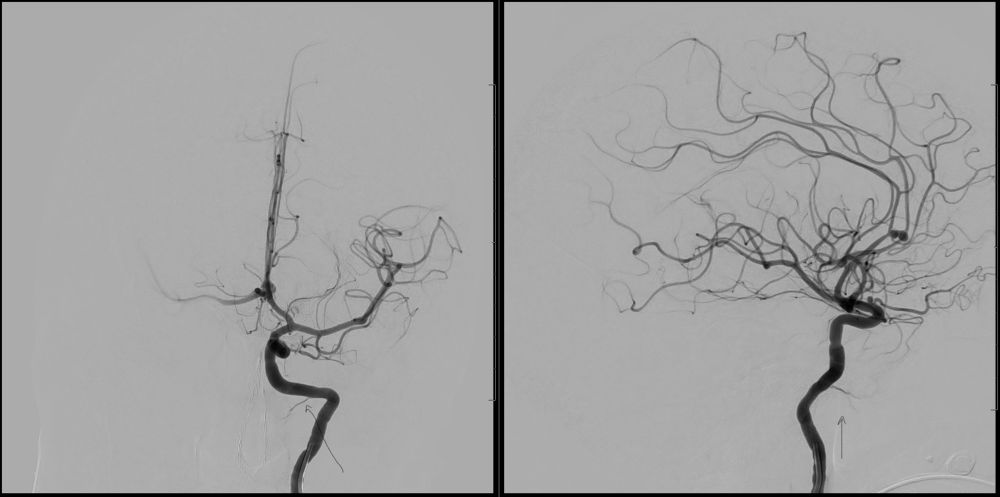

Can you describe what might be happening in this angiogram? A Left vertebral artery injection